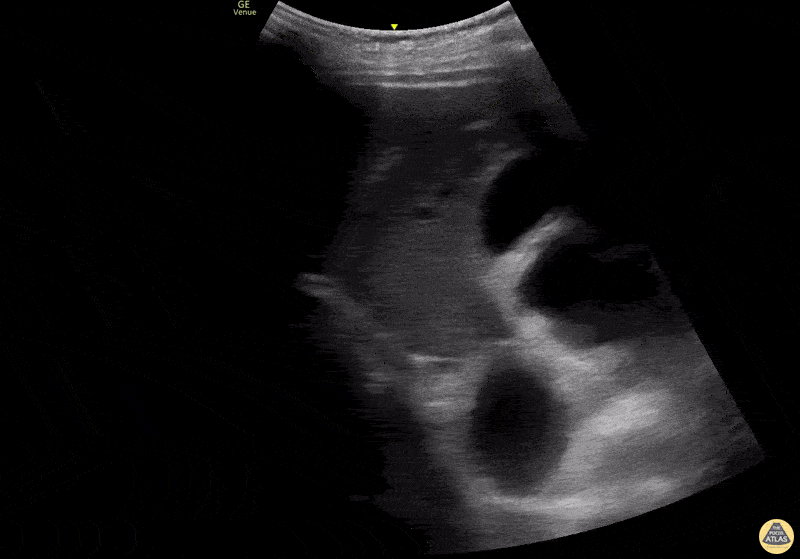

Bowel-GI - Tanga Sign (SBO)

Dilated loops of small bowel with free fluid adjacent to them (Tanga sign), CT confirmed SBO. Dimitri Livshits DO, Ultrasound Fellow; Jane Belyavskaya MD, Ultrasound Fellow; Chris Hanuscin MD, Ultrasound Division Director (Kings County/SUNY Downstate)